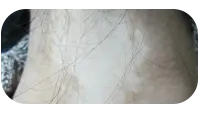

白癜风控制不住扩散通常是因为病情处于进展期且免疫活跃状态未被有效遏制,或存在持续的诱发因素刺激。常见原因包括治疗时机不当、精神压力过大、皮肤反复受外伤摩擦、暴晒、感染或内分泌波动等。进展期白癜风需要系统控制而非单纯局部治疗,若仅做光疗或外用药可能刺激扩散。关键是要及时让医生评估分期,调整控制策略,同时排查并规避生活中的诱发因素,双管齐下才能稳定病情。